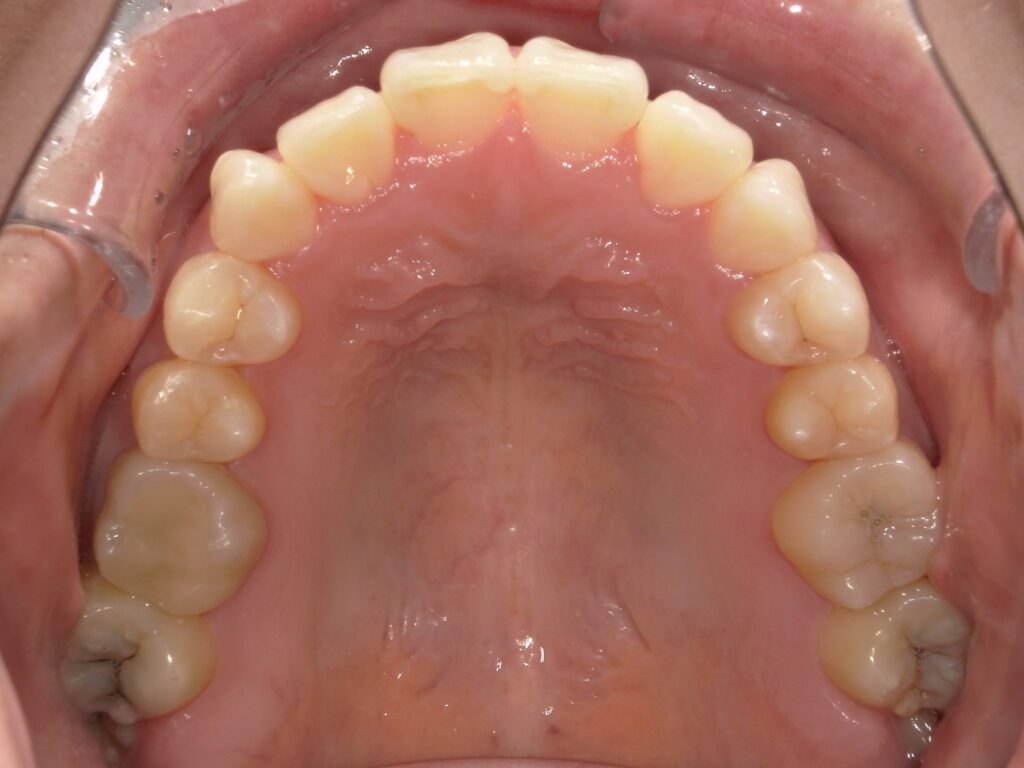

Before

After

口元の改善 / Eライン

- 20代女性

- 主訴:前歯を下げたい

- 矯正方法:インビザラインの非抜歯矯正

- 治療期間:13ヶ月

- 治療費:715,000円

- その他ご要望:歯を抜かずに口元をできる限り下げたいとのご希望。

- 詳しくはこちら

ご相談内容 前歯が出ていることが気になると20代女性からのご相談 現状と治療方針 上の前歯が出ており、口元の突出感が見られます。歯を抜くことに抵抗がある患者様だったため、奥歯をさらに後ろに下げることのできる遠心移動という方法を用いて、歯を抜かずに口元を下げる治療計画を作成しました。 治療結果 非抜歯で前歯を13ヶ月で下げることができ、横から見た際の口元の変化も見られました。 振り返り 今回の患者様は口元が出ていることにコンプレックスを感じていらっしゃり、また、歯を抜くことに抵抗もあったため、「歯を抜かずにEラインを改善する」ことができる矯正歯科を探しておられました。歯を抜かなくても口元の印象が変わったことに大変喜ばれていました。 リスク・副作用 マウスピースの装着時間を守っていただけないと矯正治療に時間がかかり、場合によっては治療がうまく進まない可能性があります。